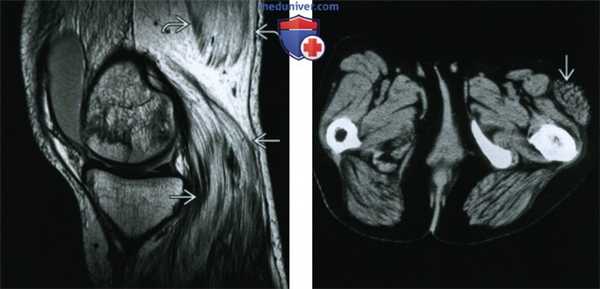

(Слева) МРТ, сагиттальный срез: исследование пациента с мышечной дистрофией. Обратите внимание на диффузное замещение икроножной и полуперепончатой мышц жировой тканью. Интересно, что эти мышцы не уменьшились в размерах и выглядят увеличенными. Эти изменения вносят вклад в увеличение икр, характерное для детей с этим заболеванием.

(Справа) КТ, аксиальный срез: определяется денервационная гипертрофия мышцы, напрягающей широкую фасцию бедра. Мышца увеличена за счет увеличения объема внутримышечной жировой ткани. Нарушения архитектоники ткани отсутствуют.